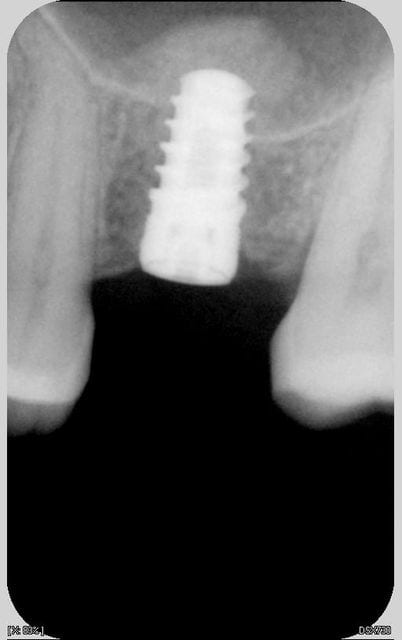

un p'tit Summers du samedi matin: sur le cliché post op on distingue le fragment de corticale qui a sauté avec le premier ostéotome.

(implant tekka progress 4.5 13, os autogène récupéré lors du forage)

at first, foret de 2 mm je m'arrete à 8 mm puis ostéotome à bout rond je fais sauter la corticale. Ensuite forage diamètre 3 sur 8 mm (je récupère l'os de forage sur mes forets). je replace l'os de forage dans le puit et avec l'ostéotome à bout plat diamètre 3 je refoule le tout à 13 mm. Enfin idem avec foret terminal. Puis mise en place de l'implant.